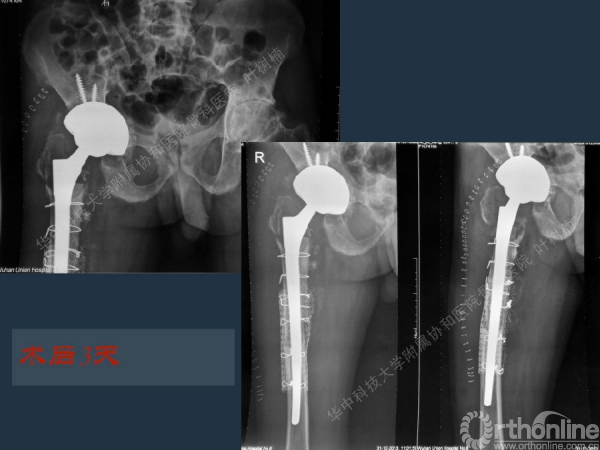

股骨侧翻修

髋臼缺损的处理